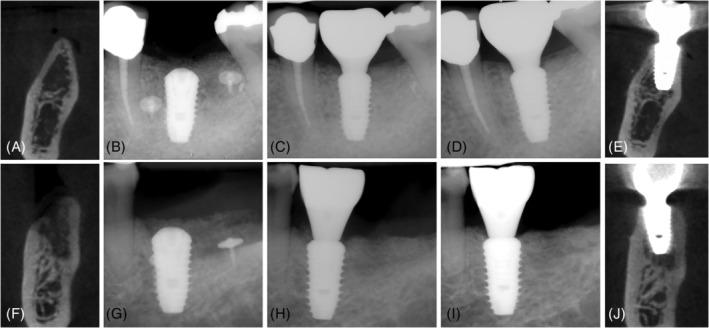

Patients with expected dehiscence defects following implant placement were randomized to use either SBS or DBBM together with a bioabsorbable collagen membrane over dehiscenced implant surfaces aimed for GBR. The changes in the bone defect size were measured before the GBR procedure and 6 months after implant placement at the re-entry surgery. Secondary outcomes included peri-implant health outcomes, implant cumulative survival rates, bone level changes, and patient-reported outcomes (PROMs) at prosthesis delivery and 1-year follow-up.

Of the 49 included patients, 24 were treated with SBS and 25 with DBBM. In the SBS group, the defect height (DH) at implant insertion was 5.1 ± 2.6 mm and was reduced at re-entry to 1.3 ± 2.0 mm (74.5%). In the DBBM group, the respective changes in DH were 4.1 ± 1.7 mm and 1.5 ± 1.9 mm (63.4%). These differences were not statistically significant (p = 0.216). The complete defect resolution rate was also comparable in both groups without statistical difference (62.5% of patients (15/24) vs. 44% of patients (11/25)). Overall, the marginal bone levels remained stable during the 1-year follow-up in both groups.